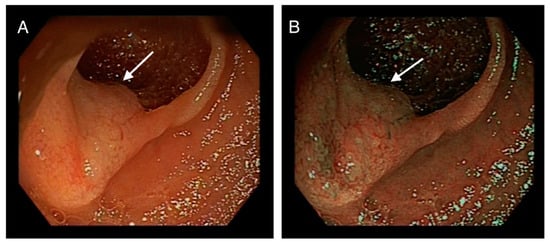

2. Case Presentation